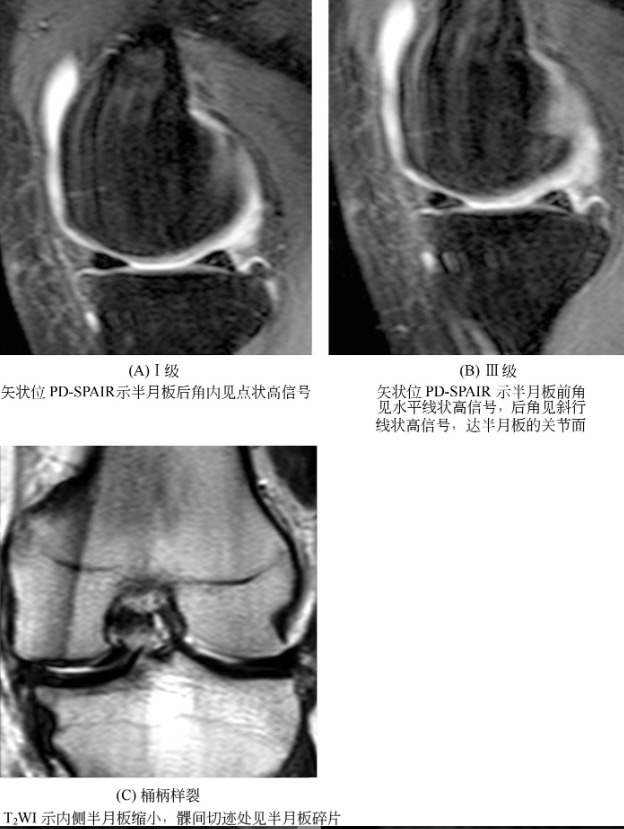

2、半月板损伤:

MRI诊断

半月板的MRI检查主要取矢状位和冠状位,前者有利于显示前后角,后者适于观察体部。正常半月板在T1WI及T2WI上均为均匀的低信号,半月板损伤表现为相对的高信号影。

病情根据高信号影的形态以及是否延及半月板上下缘分为三级:

Ⅰ级,表现为灶性圆形或椭圆形高信号影,不与关节面相接触(图7A);

Ⅱ级,水平线样高信号,可延伸至半月板的关节囊缘;

Ⅲ级,高信号达到半月板的关节面(图7B)。

桶柄样撕裂(图7C):通常发生于内侧半月板,是一种特殊的垂直纵形撕裂伴有分离,其内部的碎片(柄)移向膝关节髁间切迹,半月板体部正常的“蝴蝶结”表现消失,其周围部(桶)可表现为缩小的三角形,形成小半月板。

图7 半月板损伤。